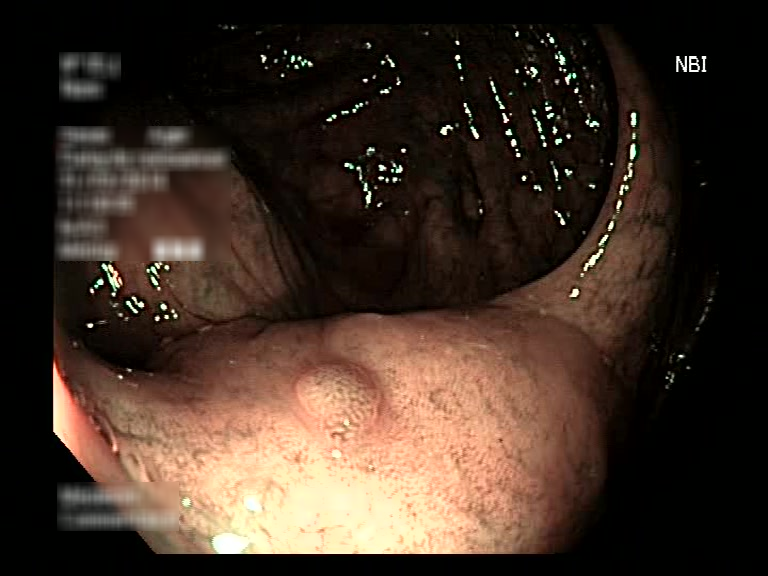

| Lesion | White Light Frame | NBI Frame | White Light Video | NBI Video | Camera Calibration |

| serrated_01 |  |

|

WL.mp4 | NBI.mp4 | cam.xml |